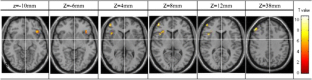

Functional Magnetic Resonance Imaging (fMRI) of inhibitory control has only been investigated in patients with attention deficit hyperactivity disorder (ADHD) and conduct disorder (CD). The objective of this study was to investigate the differences of functional areas associated with inhibitory control between boys with pure oppositional defiant disorder (ODD) and controls during a response inhibition task using functional magnetic resonance imaging (fMRI). Eleven boys with pure ODD and ten control boys, aged 10 to 12, performed a GoStop response inhibition task in this study. The task has a series of “go” trials to establish a pre-potent response tendency and a number of “stop” trials to test subjects’ ability to withhold their responses. During the GoStop task, greater activation in the dorsolateral parts of the bilateral inferior frontal gyrus, left middle frontal gyrus (lMFG) and right superior frontal gyrus (rSFG) activation was seen in the ODD boys. Additionally, reduced activation in regions of the right inferior frontal gyrus (rIFG) was seen in the ODD boys in comparison with the control group. The results may suggest that the higher activation in areas adjacent to the rIFG could be the cause of reduced activation in the rIFG; although this is speculative and requires additional supporting evidence. The findings further suggest that ODD is a less pronounced functional disorder compared to ADHD and CD.

Fig. 3